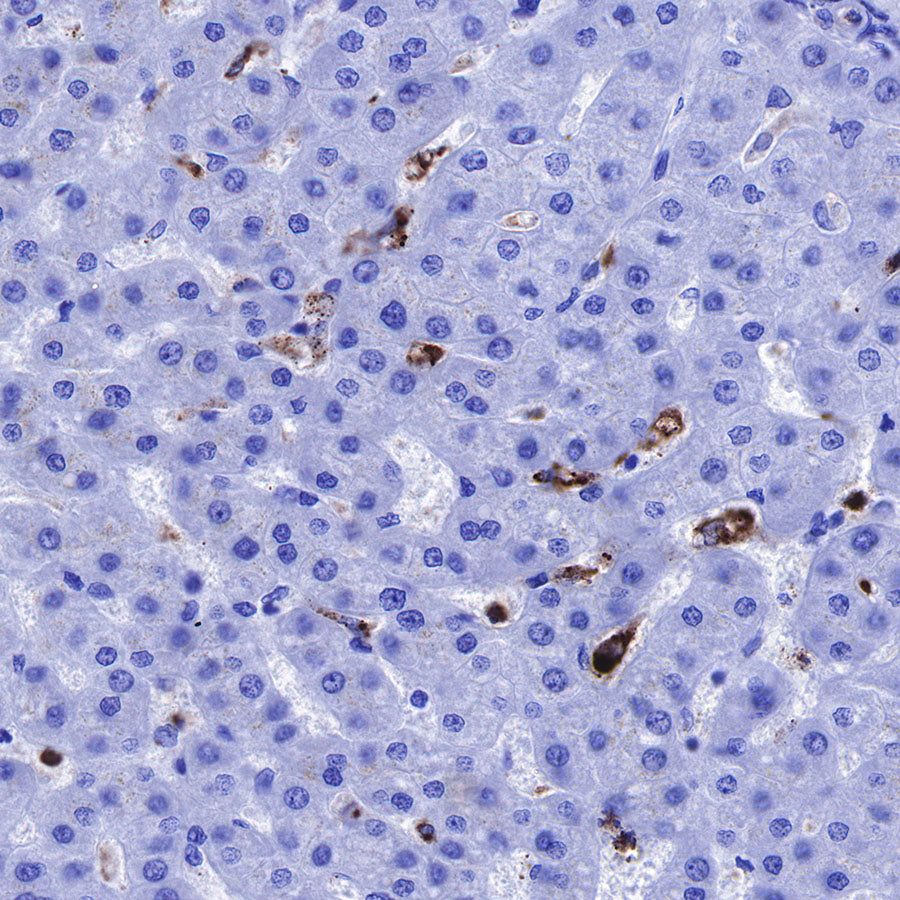

Immunohistochemistry

IHC shows positive staining in paraffin-embedded human liver. Anti-Lysozyme antibody was used at 1/100 dilution, followed by a HRP Polymer for Mouse & Rabbit IgG (ready to use). Counterstained with hematoxylin. Heat mediated antigen retrieval with Tris/EDTA buffer pH9.0 was performed before commencing with IHC staining protocol.